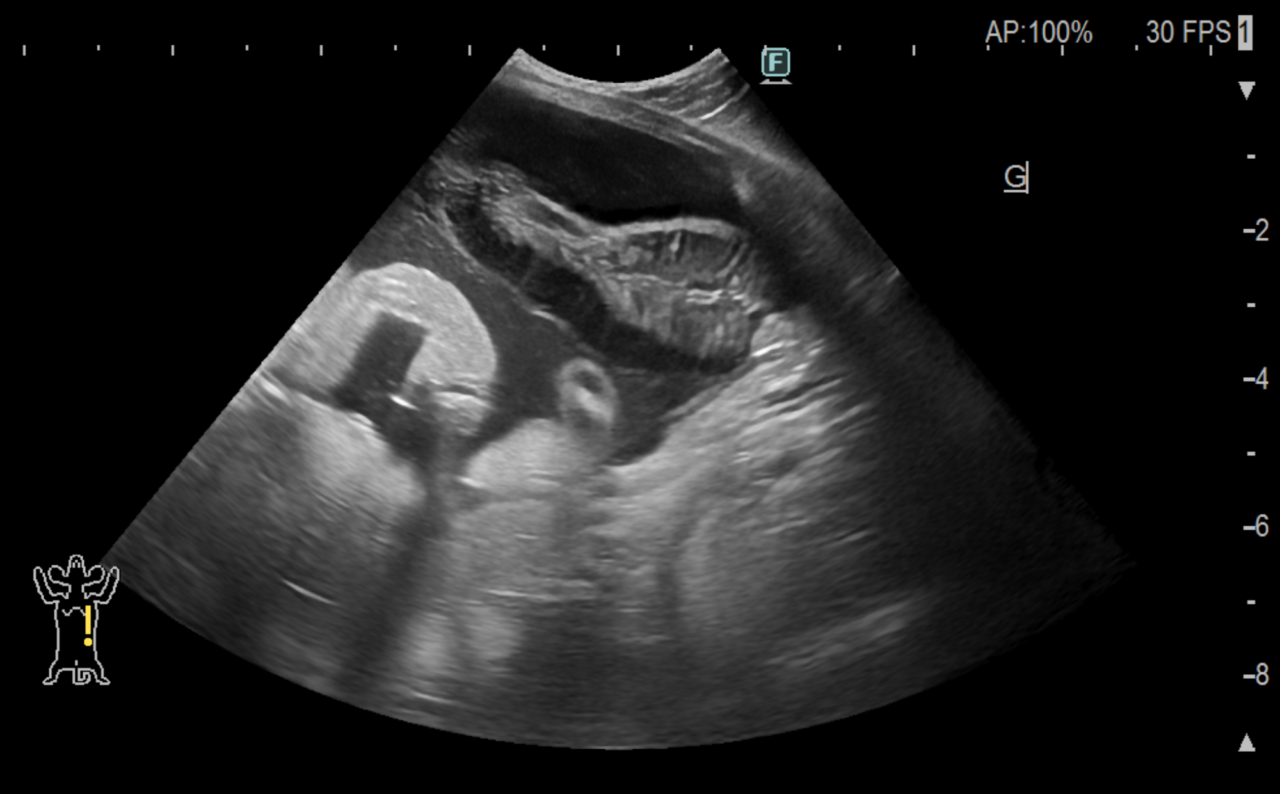

本来胆嚢があるべきところには胆嚢が確認できず、下腹部に以上なエコー像が複数確認でき、胆嚢粘液嚢腫が破裂したと判断しました。